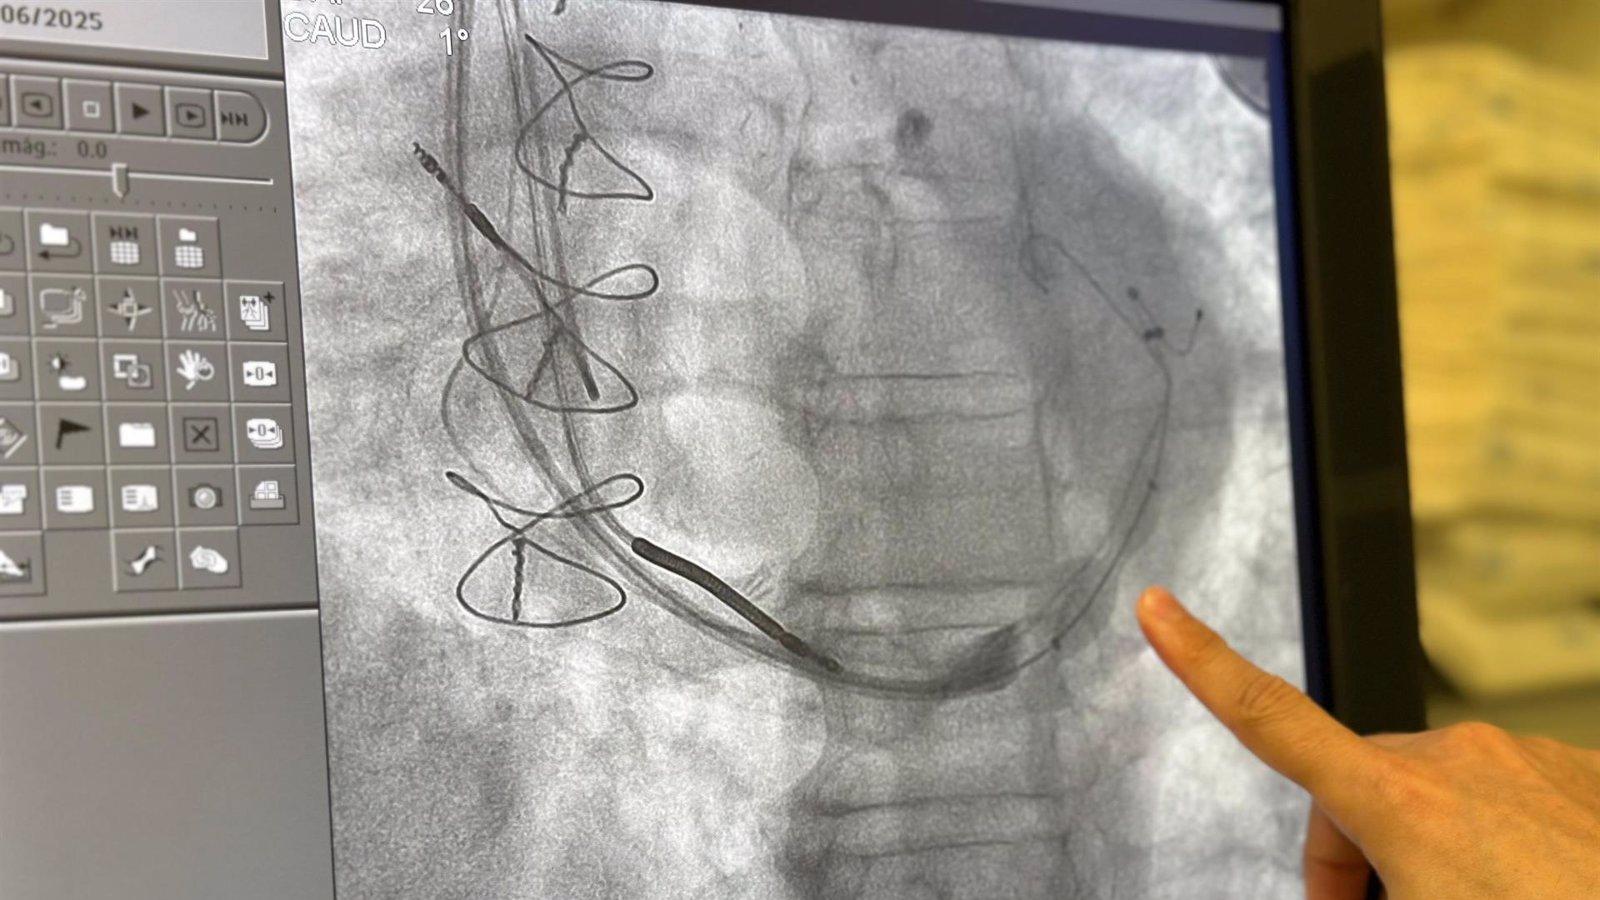

El Servicio de Cardiología del Hospital de Torrejón ha llevado a cabo con éxito la primera implantación de un dispositivo reductor del seno coronario (Reducer) en un paciente afectado por angina refractaria, una dolencia cardíaca que provoca dolor torácico persistente resistente a los tratamientos convencionales. La intervención sitúa al centro madrileño a La Vanguardia en el tratamiento de patologías coronarias complejas.

El dispositivo implantado, de pequeño tamaño y forma de reloj de arena, se coloca en la vena principal del corazón para aumentar ligeramente la presión en esa zona, mejorando así el flujo sanguíneo hacia las áreas del miocardio que no reciben suficiente oxígeno. Esta solución está diseñada específicamente para pacientes que, por su situación clínica, ya no son candidatos ni a cirugía ni a angioplastia.

El paciente tratado presentaba una enfermedad coronaria avanzada, con múltiples intervenciones previas, entre ellas varios stents y puentes aortocoronarios, además de una afectación en vasos de pequeño calibre. Asimismo, contaba con un desfibrilador resincronizador implantado, lo que incrementaba significativamente la dificultad técnica del procedimiento.